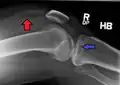

A tibial plateau fracture is a break of the upper part of the tibia (shinbone) that involves the knee joint.[1] Symptoms include pain, swelling, and a decreased ability to move the knee.[1] People are generally unable to walk.[2] Complication may include injury to the artery or nerve, arthritis, and compartment syndrome.[1]

| A severe tibial plateau fracture with an associated fibular head fracture | |

In all injuries to the tibial plateau radiographs (commonly called x-rays) are imperative. Computed tomography scans are not always necessary but are sometimes critical for evaluating degree of fracture and determining a treatment plan that would not be possible with plain radiographs.[5] Magnetic Resonance images are the diagnostic modality of choice when meniscal, ligamentous and soft tissue injuries are suspected.[6][7] CT angiography should be considered if there is alteration of the distal pulses or concern about arterial injury.

A tibial plateau fracture seen on X-ray